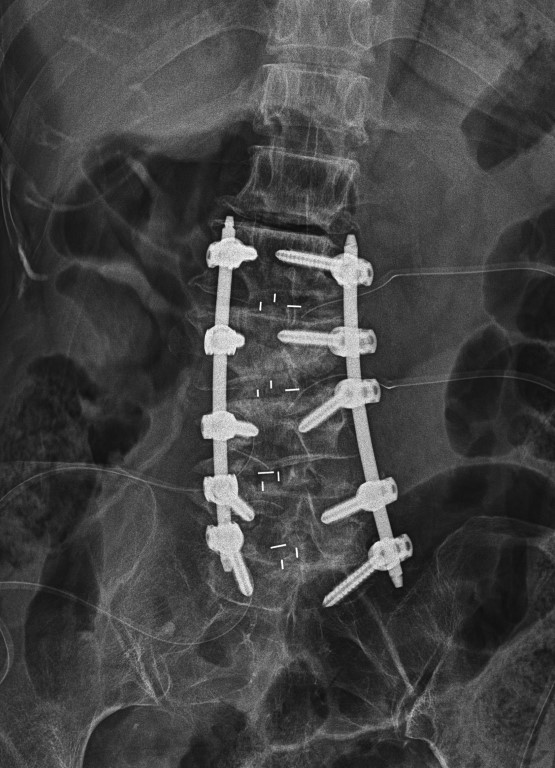

양방향 척추 내시경을 통해

디스크 하나하나에

케이지를 삽입하여

추간공 간극을 벌리는 작업을 진행하였구요

내시경으로 감압과 동시에

추간공을 확공하니

신경통로에 대한 확보 및

측만증 정렬도 반듯하게

되는 수술을 진행하였습니다

수술을 마치고는

4마디에 대해서

최소침습 나사못 고정으로

마무리를 진행하였구요

수술 전에 비해

측만증도 해결이되고

추간공 감압술도 해결, 중심협착증도 정리가 된

결과를 볼 수 있게 되었습니다

이 모든 것이 양방향 척추 내시경을 통해서 진행되었습니다